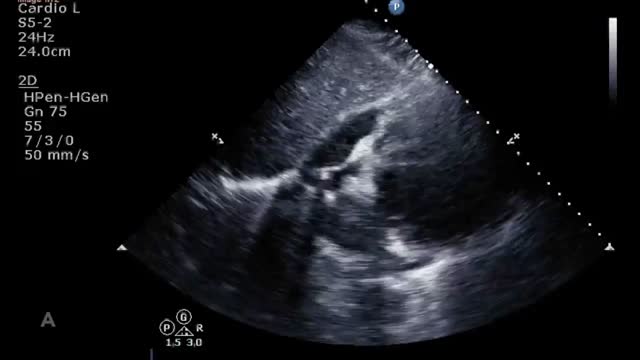

Al iniciar el soporte, la ETT/ETE nos permitirá evaluar la situación, el tamaño y el grado de descompresión de las cavidades cardiacas, la posición septal como expresión de la interdependencia ventricular, evaluar el estado de volemia/precarga que pueda comprometer el flujo de la ECMO y el desarrollo de posibles complicaciones precoces como es el desarrollo de derrame pericárdico, el cierre valvular aórtico o el aumento de insuficiencias valvulares por el aumento de la poscarga del VI que condiciona la ECMO30.

Manejo del paciente con ECMO veno-arterialDebemos tener en cuenta que la mayor parte de los sistemas de monitorización (termodilución transpulmonar, análisis de contorno de pulso) están artefactados por el efecto hemodinámico de la ECMO, por lo que debemos incluir la ETT/ETE en la evaluación diaria de estos pacientes. Mediante esta exploración podremos valorar y comparar con la exploración basal15:

El tamaño y contractilidad biventricular que nos indique la evolución de la función cardiaca por la que se instauró la ECMO.

La presencia de signos ecocardiográficos (relación E/A, pendiente de desaceleración de la onda E, relación E/e’) de altas presiones telediastólicas izquierdas que nos indique una inadecuada descarga ventricular.